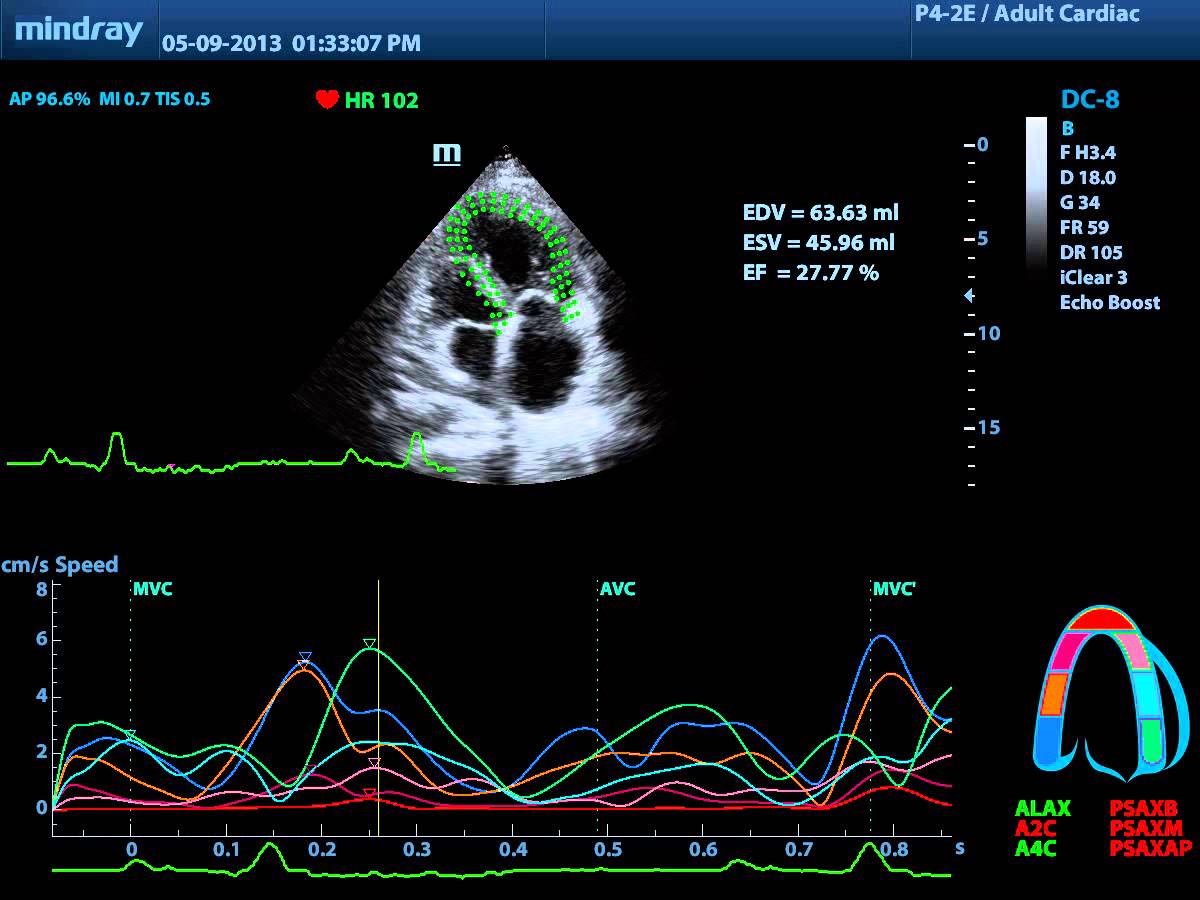

Tissue Tracking (speckle tracking) - количественная оценка движения и деформации миокарда  на основе трехмерной регистрации смещения сегментов миокарда сердца

Tissue Tracking – это ультразвуковая методика для точной количественной оценки сократительной функции миокарда, его количественной оценки в ручном и автоматическом режиме. Методика основана на пространственном отслеживании (трекинге) спеклов стенок миокарда в течении полного цикла сокращения сердца.

Данный метод является новым и перспективным. В мировой специальной литературе все чаще и чаще приводятся данные о диагностических исследованиях методом speckle-tracking. Главными преимуществами данного метода является не только высокая точность, но и практически полное отсутствие такого же быстрого и дешевого в применении метода для аналогичных оценок. До внедрения в практику метода автоматического отслеживания спекл –зон эхограмы и проведения количественного анализа, подобные исследования можно было выполнить только на аппаратах магнитно-резонансной терапии (МРТ) с использованием специальных средств для отслеживания движения молекул в стеках миокарда. Безусловно, применение МРТ в «рутинных» каждодневных исследованиях осложнено низкой пропускной способностью МРТ-диагностики и, что гораздо важнее, стоимостью применения этой методики.

Сегодня технология количественной оценки движения и деформации миокарда с помощью ультразвукового диагностического прибора не имеет конкуренции и все чаще встречается в кабинетах экспертной ультразвуковой диагностики.

Ниже представлено изображение, полученное с помощью прибора Mindray DC-8 в режиме Tissue Tracking.